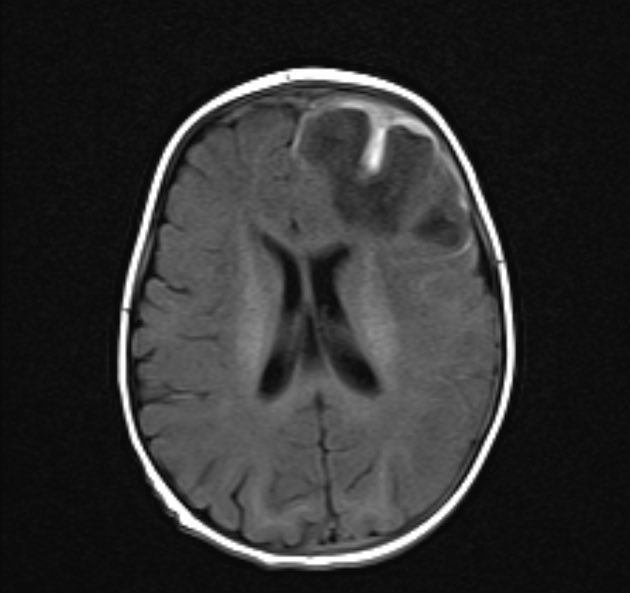

👱‍♀️58F with 2 weeks of confusion, behavioral change, and seizures. Labs unremarkable, renal function normal. 🍴On MRI I see… a fork? 👀What do you see?

@nirmalregency Fair point. This case is better called autoimmune encephalitis, not limbic encephalitis. No mesial temporal involvement on MRI. “Autoimmune” defines etiology. “Limbic” defines location. Using “autoimmune limbic encephalitis” as a blanket term is misleading.